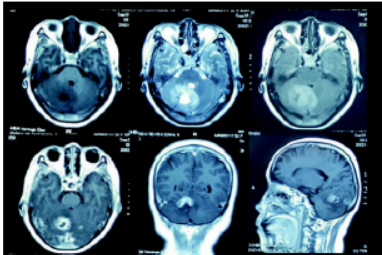

患者董某某,女性,53岁,言语不清40余天。既往有高血压,糖尿病,精神分裂症病史。查体:神志清楚,对答切题,言语含糊,闭目难立、轮替试验等均正常,四肢肌力、肌张力正常,双侧病理征阴性。血常规、肝肾功能、电解质均正常。胸部CT未见明显异常。头颅MRI提示:右侧小脑上部短T1,长T2信号肿块影,边界不清晰,周边可见水肿带,肿瘤大小约2×2×1.5 cm。肿瘤增强后呈不均匀环形强化(图1、2)。入院诊断:右侧小脑肿瘤。

图1 MRI平扫T1呈低信号,T2呈高信号,FLAIR呈稍高信号,增强呈不均匀强化。

图2 患者的MRS提示:NAA明显下降,Cho明显升高

PCNSL典型的临床表现主要是逐渐进展的局灶性症状,包括颅内压增高、局灶性神经功能缺损、精神状态改变;有少量文献报道,病变可侵及眼球,引起视力下降、视物模糊等症状。PCNSTL的临床表现及预后与PCNSL是相类似的。PCNSL的磁共振表现为单发或者多发病灶,T1WI表现为脑灰质样的等信号或者稍低信号,T2WI表现为等信号或稍高信号;DWI及ADC图上表现为扩散受限的改变,即DWI稍高信号,ADC值下降;MRS表现为NAA峰值变低,并可见脂质峰;增强扫描表现为明显的均匀强化;瘤周水肿与肿瘤的大小不成比例,一般瘤周水肿和占位效应较轻。